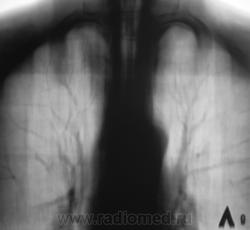

Взяли на контроль.  Какие мнения будут по поводу наличия/отсутствия специфического процесса.

Произвели стандартное дообследование.